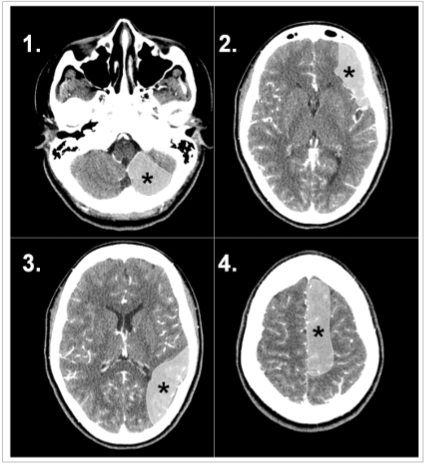

A doença vascular encefálica isquêmica pode determinar diferentes síndromes clínicas a depender do território arterial acometido. A percepção destas síndromes clínicas informadas no pedido médico pode auxiliar o radiologista na percepção de sinais precoces de isquemia intracraniana.

Com base na análise das imagens apresentadas, o território arterial acometido e as respectivas síndromes clínicas proporcionadas são, respectivamente:

As imagens a seguir referem-se a dois pacientes diferentes, previamente hígidos, com traumatismo cranioencefálico.

Em relação às características das lesões intracranianas evidenciadas tem-se que: